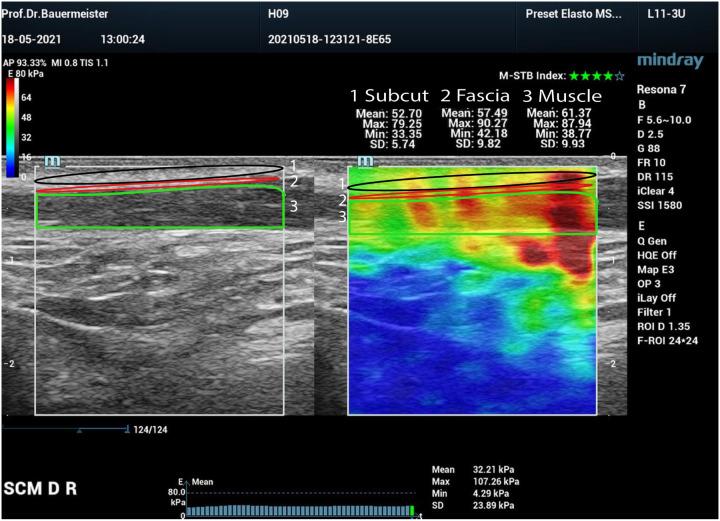

Cervical fibrosis (CF) as a late consequence in patients after radiotherapy significantly impacts the long-term symptoms, functionality, and quality of life of these cancer patients due to a hardening process of different histological tissues. Modern Shear Wave Ultrasound Elastography now enables a differentiated analysis of the changes in various tissue types. In this study, tissue-specific changes in CF induced by radiation therapy in head and neck (ENT) cancer patients were quantified and correlated with cervical range of motion (CROM).

MATERIALS AND METHODS

16 patients after radiation of the cervical lymphatic drainage were selected as the observation group (OG). Further, 16 people without radiation in the head and neck region were matched by gender, age, and BMI as the control group (CG). Stiffness measurements in kilopascal (kPa; 1 Pa = 1 N m) were performed using shear wave elastography (SWE) to assess the elasticity of muscle, fascia, and subcutaneous tissue within and surrounding the sternocleidomastoid muscle (SCM). Specific parameters of the OG were compared to the CG and correlated with functional parameters and quality of life (QoL).

RESULTS

The OG exhibited significantly higher stiffness values (Emean, Emax, Emin) across all tissue types than the CG, suggesting a tangible effect of radiation therapy on tissue stiffness. Muscle compartment analysis revealed the most significant stiffness differences. Thickness measurements indicated changes in the muscle and skin but not in the subcutaneous tissue. CROM measurements within the OG fell within normal ranges, suggesting a possible homogenizing effect of radiation treatment on CROM variability. Strong correlations were observed between age and specific stiffness measures, particularly in the OG group, indicating a broader impact of aging or radiation therapy on physiological measures. Significant correlations between tissue stiffness and CROM were found.

CONCLUSION

CF after radiotherapy occurs primarily in the muscle tissue and its fascia, with the hardening being about twice as pronounced as in the average population and becoming more pronounced with increasing age and correlates with CROM.

颈部纤维化(CF)作为放疗后患者的晚期后果,由于不同组织学组织的硬化过程,会显著影响这些癌症患者的长期症状、功能和生活质量。现代剪切波超声弹性成像技术现在能够对各种组织类型的变化进行差异化分析。在本研究中,对头颈部(耳鼻喉科)癌症患者放疗引起的CF组织特异性变化进行了量化,并与颈部活动范围(CROM)相关联。

材料与方法

选择16例接受颈部淋巴引流放疗的患者作为观察组(OG)。此外,选取16例头颈部未接受放疗的患者,按照性别、年龄和体重指数进行匹配,作为对照组(CG)。使用剪切波弹性成像(SWE)以千帕(kPa;1 Pa = 1 N/m)为单位进行硬度测量,以评估胸锁乳突肌(SCM)内及其周围肌肉、筋膜和皮下组织的弹性。将OG的特定参数与CG进行比较,并与功能参数和生活质量(QoL)相关联。

结果

与CG相比,OG在所有组织类型中均表现出显著更高的硬度值(Emean、Emax、Emin),表明放疗对组织硬度有明显影响。肌肉隔室分析显示硬度差异最为显著。厚度测量表明肌肉和皮肤有变化,但皮下组织无变化。OG内的CROM测量值在正常范围内,表明放疗对CROM变异性可能有均匀化作用。观察到年龄与特定硬度测量值之间存在强相关性,尤其是在OG组中,表明衰老或放疗对生理测量有更广泛的影响。发现组织硬度与CROM之间存在显著相关性。

结论

放疗后CF主要发生在肌肉组织及其筋膜中,硬化程度约为普通人群的两倍,且随着年龄增长而更加明显,并与CROM相关。